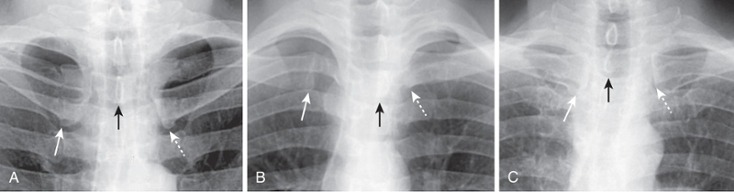

Close-up view of the heads of the clavicles demonstrates that each (solid white arrow for right and dotted white arrow for left) is about equidistant from the spinous process of the vertebral body between them (black arrow). This indicates the patient is not rotated.

Close-up view of the heads of the clavicles in a patient rotated toward his own right (remember that you are viewing the study as if the patient were facing you). The spinous process (black arrow) projects much closer to the left clavicular head (dotted white arrow) than to the right clavicular head (solid white arrow).

Close-up view of the heads of the clavicles in a patient rotated toward his own left. The spinous process (black arrow) is much closer to the right clavicular head (solid white arrow) than it is to the left (dotted white arrow).